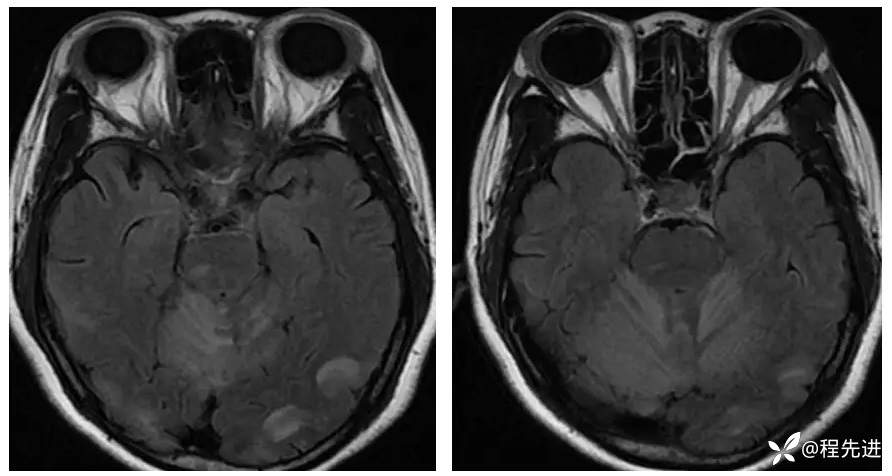

【现病史及既往史】:孕期38周,蛋白尿10天,血压升高6天,剖腹产后一天出现头晕,头痛,嗜睡。既往糖尿病史

查体:不配合,血压波动,130-157/85-109mmHg

影像检查: